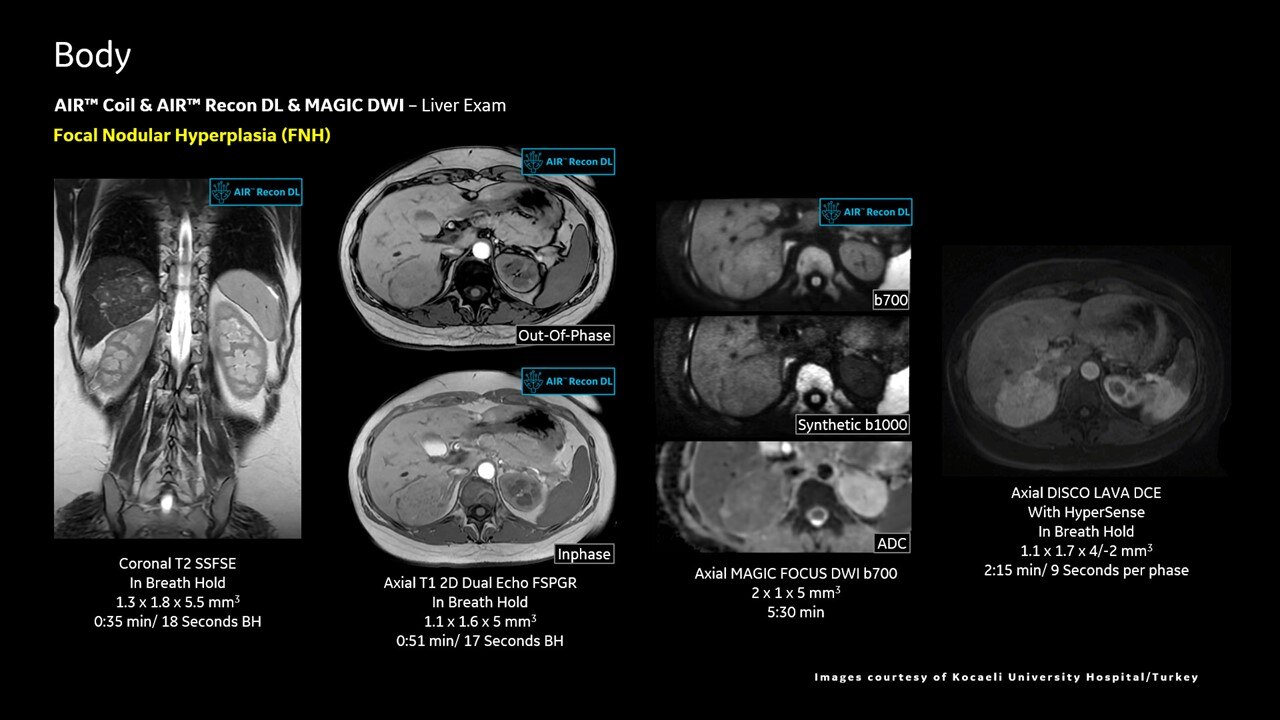

AIR™ Recon DL improves SNR and image sharpness, enabling shorter scan times

Achieve a 25% efficiency gain with Ultra High Efficiency (UHE) gradient system. Fast, clear Total Digital Imaging (TDI) increases SNR by 25%. Improved IQ in 80% of cases without added time. Acquire higher SNR without a time penalty and get images virtually free of artifact with AIR™ Recon DL.***